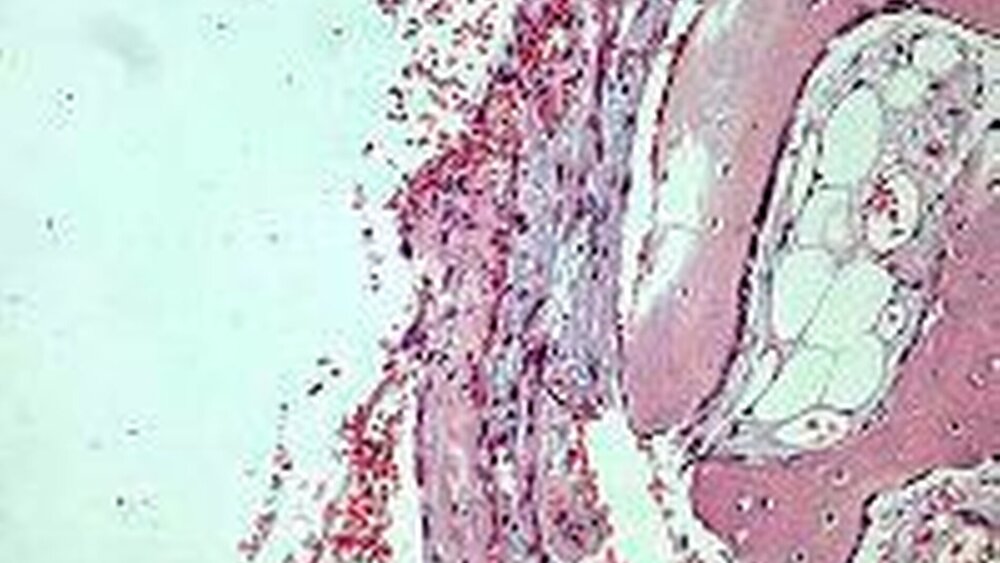

Zur Abklärung der Osteotomie wurde die Außenfläche des Unterkiefers über eine marginale Schnittführung dargestellt und ein Knochendeckel entnommen. Darunter befand sich eine leere Knochenhöhle. Die Höhle wurde vorsichtig ausgetastet und kürettiert. Der Knochendeckel, der die äußere Begrenzung des knöchernen Hohlraums bildete, wurde zur histologischen Untersuchung eingesendet. Im histologischen Bild zeigte sich, dass der Hohlraum von einer dünnen Bindegewebsschicht ohne Epithel ausgekleidet war (Abb. 4). Dieser Befund entspricht einer so genannten einfachen Knochenzyste oder Knochenkavität.